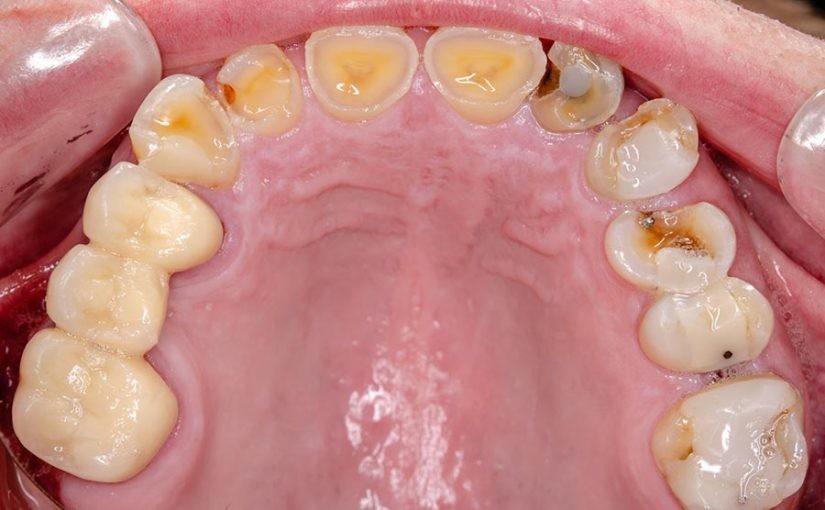

The most common causes of a dental abrasion are due to brushing the teeth too vigorously, improperly flossing the teeth, chewing tobacco and biting down on hard objects like fingernails, bottle caps, pens and more. Other causes of dental abrasions include frequently using toothpicks and frequently removing and setting any dental appliances inside the mouth. Usually, the teeth that are most often affected by dental abrasions are the canines and premolars. As a result of dental abrasion, the teeth might become more sensitive to hot and cold temperatures as well as sweet or acidic foods and drinks. If the dentin underneath the enamel is exposed, then the pain could be increased since the dentin is where the nerves and blood vessels of the tooth reside.

There are a couple of different ways to determine whether or not you have a dental abrasion on one or more of your teeth. The way that many dentists check for dental abrasions is by holding a light up to the teeth. Because enamel is translucent, light can be seen through it. The way that individuals can check for dental abrasion on their own is by examining their teeth and looking for any signs of V-shapes on the teeth that can indicate excessive pressure during brushing. Abrasions are visible on the cervical necks of the teeth, and they look like deep ridges. Instead of having the carious appearance that enamel usually has, it will have a shiny appearance, which indicates that some of the dentin is exposed. In some severe cases of dental abrasion, sometimes the ridge is even deep enough to see the pulp of the tooth itself.